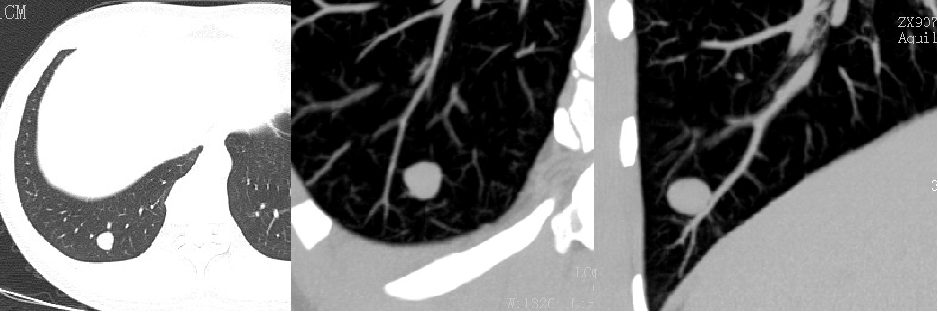

实性结节:

磨玻璃结节:

部分实性结节: